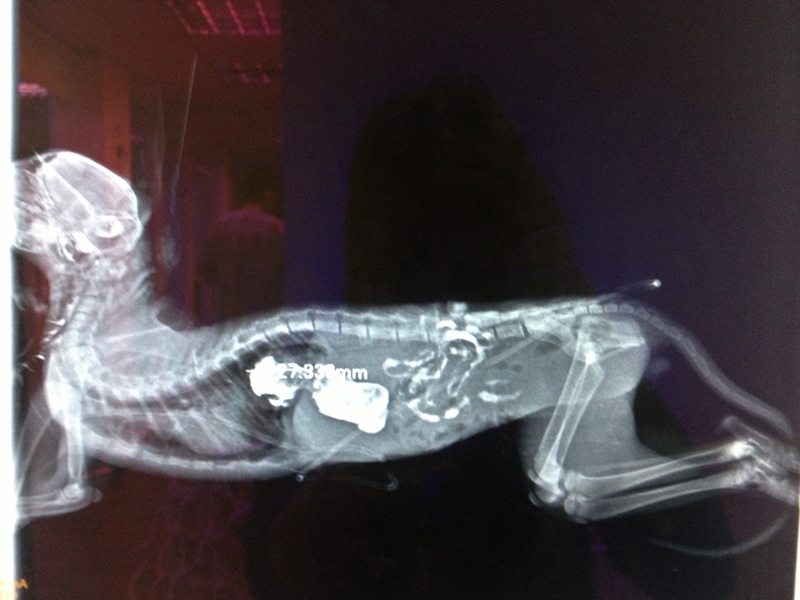

主題: 橫膈膜破裂的小橘貓 申請者姓名: Princess Quintela 花色: 申請日期: 2013-07-13 14:19:51 申請者部落格: 申請者臉書網址: https://www.facebook.com/media/set/?set=a.312351008900272.1073741829.298243480311025&type=1 所在縣市/合作醫院: 台北市/極光動物醫院 治療費用: 35870元 需求人數: 38人 已結案 (2013-09-03 16:27:37) 報名人員: 李玉君(已付款)、流浪媽 x3(已付款)、黃小歐 x2(已付款)、Alice Wu(已付款)、Jill Tsou、Winnie Chen(已付款)、白欣田(已付款)、Jill Tsou、iMADOKA(已付款)、Penly(已付款)、Kimi Hsu x2(已付款)、sammi lin(已付款)、茶茶(已付款)、caroline(已付款)、于葳、李昭慧(已付款)、Hlyo(已付款)、virginia(已付款)、izzue0622(已付款)、beforn(已付款)、王家勝&多多、chiawei(已付款)、Soso Chiang、Soso Chiang(已付款)、Ashley Huang(已付款)、Hsu Wei Ting(已付款)、林嘉南(已付款)、Princess Quintela x2(已付款)、林加一(已付款)、Kayla Chen(已付款)、鄧步步(已付款)、林慧美、Arthur Jo(已付款)、林慧美、林慧美、TOM WANG(已付款)、ztsai(已付款)、Weirong(已付款)、小貓(已付款)、Sandy、meemee(已付款)、Liwing Lin(已付款)、 候補人員: Nicky、Steffi Hsieh、 動物病情說明: 求助事項說明(請詳述貓咪狀況):於2013/06/28晚間於樹林中正路天橋馬路上看到一隻小喵,驚恐的在閃避車子,因其躲藏地點在天橋下,發現天橋下有破箱子,和些許水,跟人類食物剩菜,打掃阿姨告知是遭人棄養,發現其瘦弱不堪因此帶回照顧,並做驅蟲和耳朵清潔,後發現小橘子呼吸不穩定,2013/06/30照X光,醫師診斷為橫膈赫尼亞,橫膈膜破裂,腸胃等器官都跑到胸腔,壓迫到心臟和肺部,需要開刀將腸胃復原正常位置,否則將引起呼吸困難及運動不耐等症狀,並可能因為創傷呈現急性休克的現象。2013/07/03帶去協會指定的極光動物醫院檢查,醫師表示當天安排住院及手術準備。2013/07/04進行第一次手術,將橫膈膜縫補並將臟器歸位,手術過程順利。2013/07/05拔胸管時發現有異常現象,於是進行第二次手術,過程順利。2013/07/08醫院通知已可出院。 動物近況說明: 小橘子手術後恢復狀況良好,食慾變好了,喘氣也不再那麼快速,也沒有呼吸困難現象,